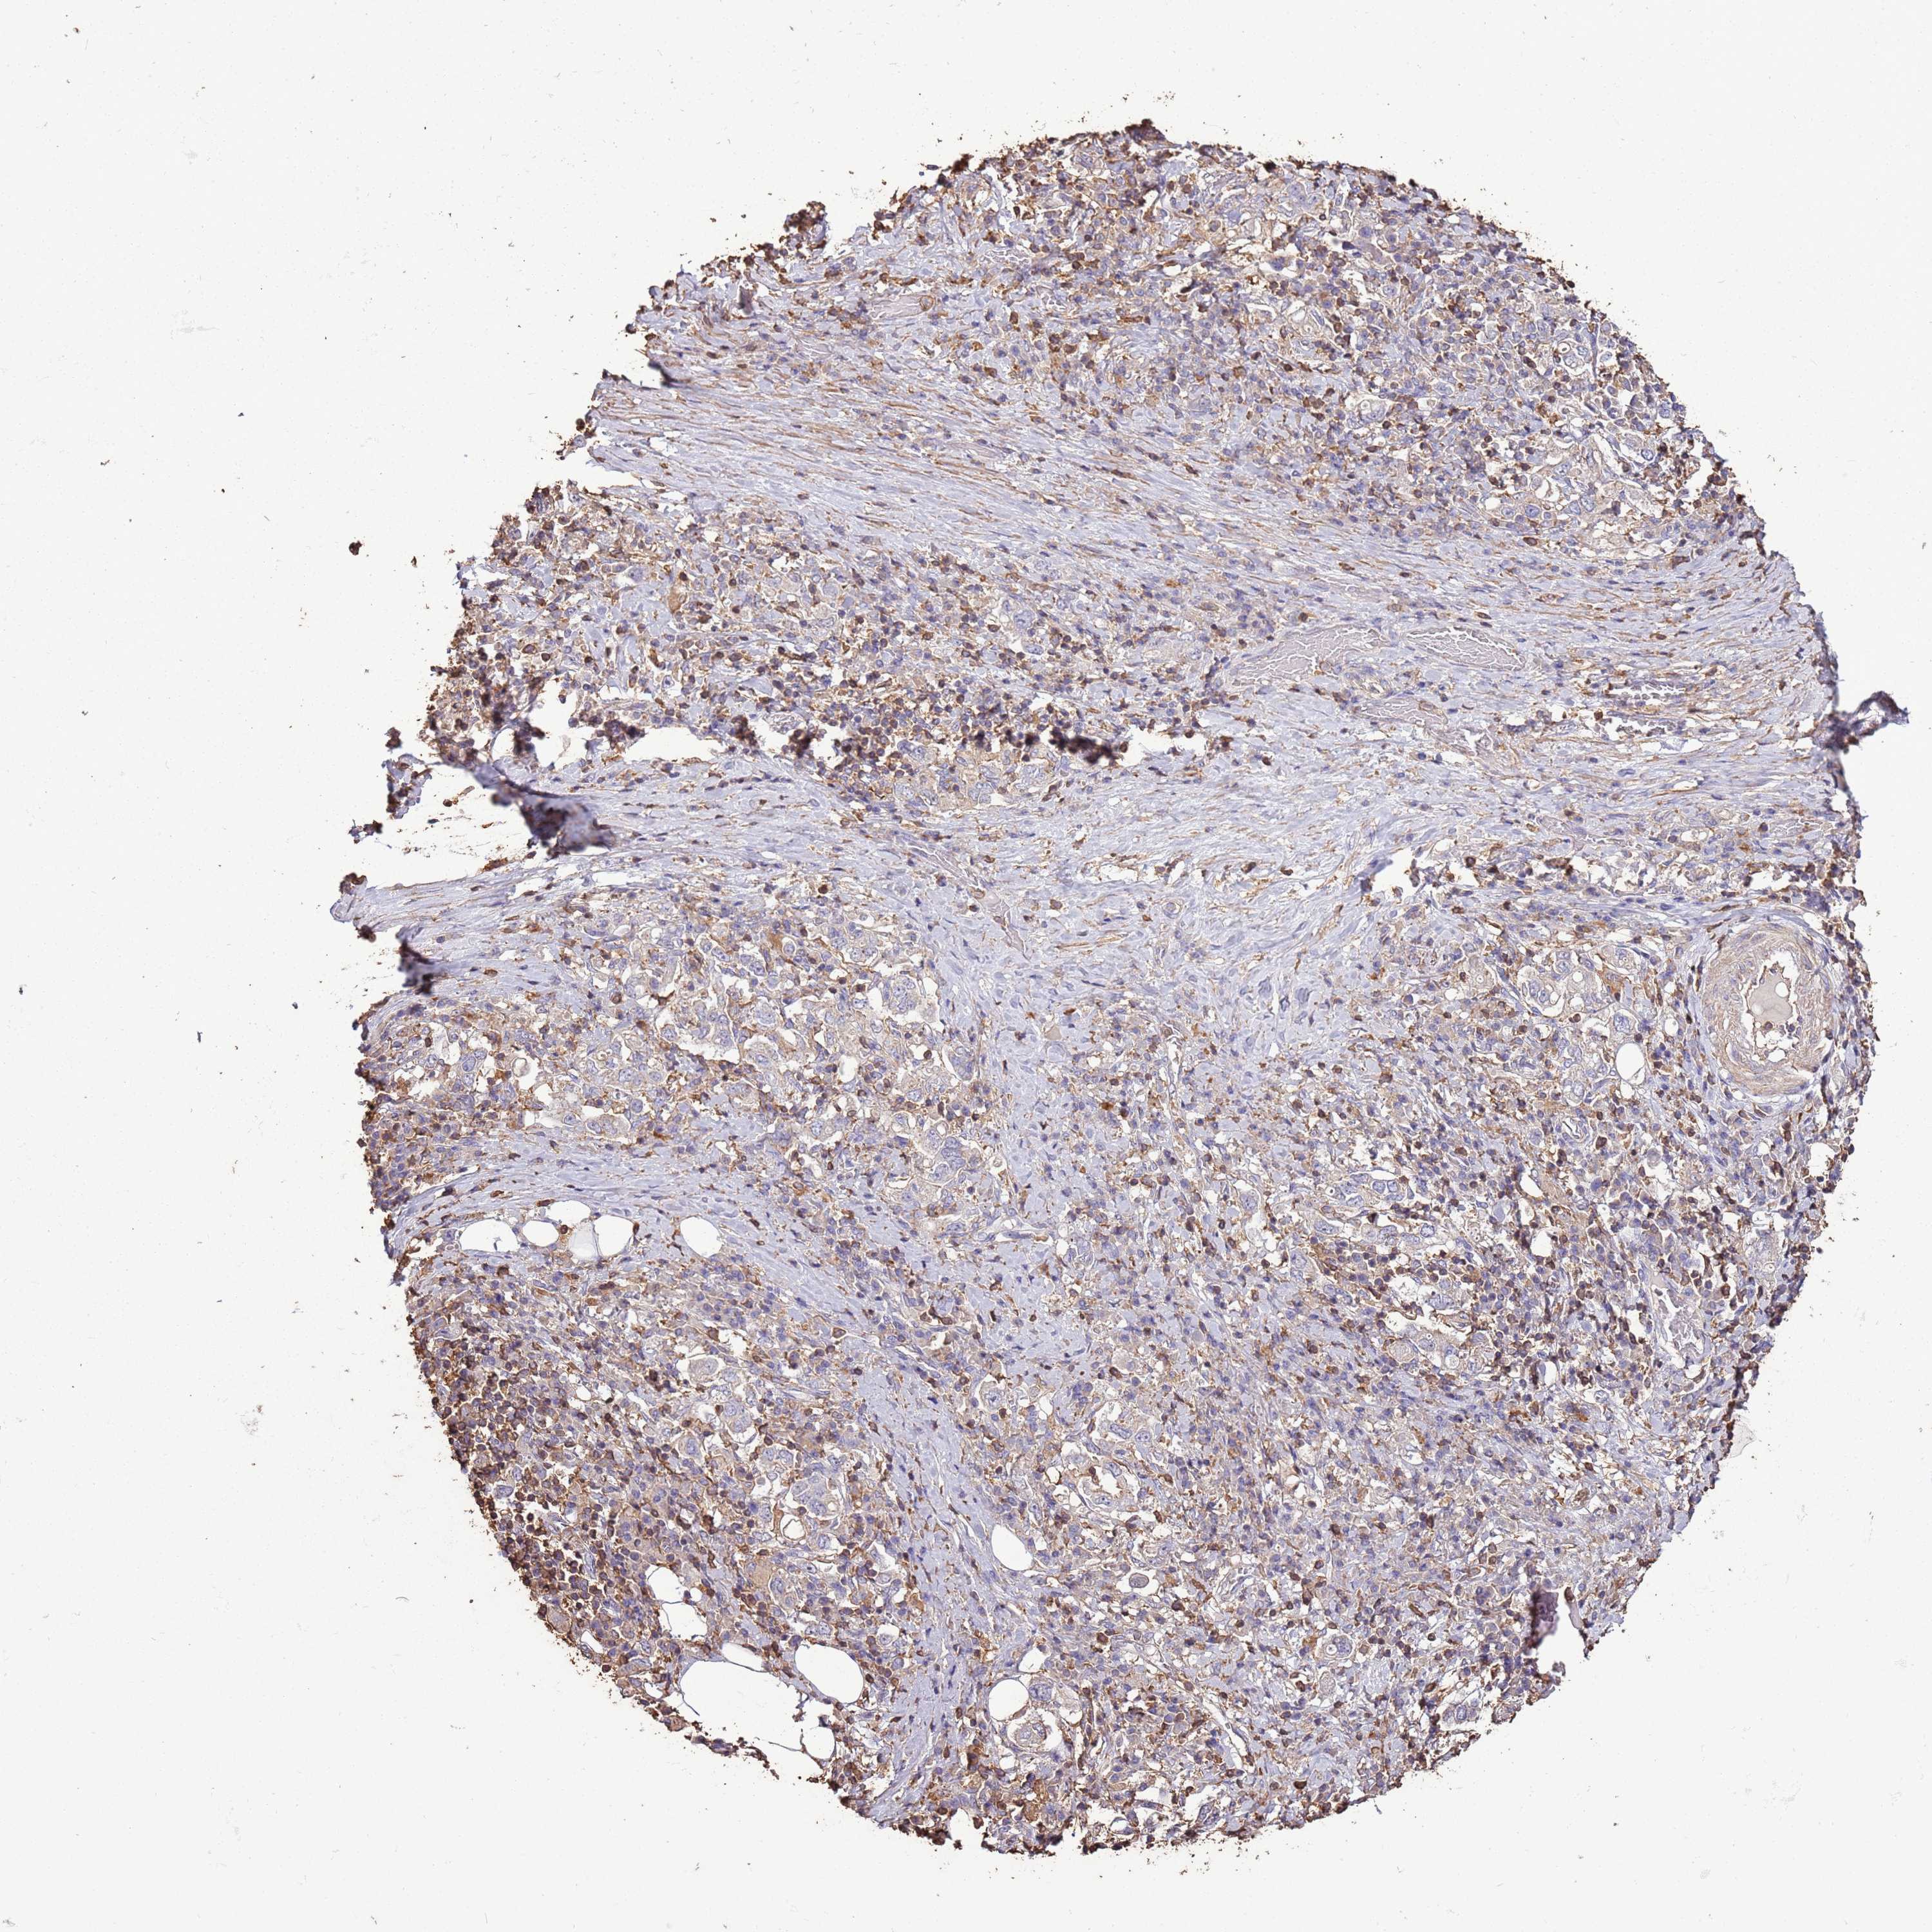

STOMACH CANCER - Protein expressioni

A mouse-over function shows sample information and annotation data. Click on an image to view it in a full screen mode. Samples can be filtered based on level of antibody staining by selecting one or several of the following categories: high, medium, low and not detected. The assay and annotation is described here.

Note that samples used for immunohistochemistry by the Human Protein Atlas do not correspond to samples in the TCGA dataset.

Antibody stainingi

Antibody staining in the annotated cell types in the current human tissue is reported as not detected, low, medium, or high, based on conventional immunohistochemistry profiling in selected tissues. This score is based on the combination of the staining intensity and fraction of stained cells.

Each image is clickable and will lead to virtual microscopy that enables deeper exploration of all samples and also displays staining intensity scores, fraction scores and subcellular localization as well as patient and tissue information for each sample.

Antibody HPA047044

Staining

High

Medium

Low

Not detected

Intensity

Strong

Moderate

Weak

Negative

Quantity

>75%

75%-25%

<25%

None

Location

Nuclear

Cytoplasmic/membranous

Cytoplasmic/membranous,nuclear

Adenocarcinoma, NOS